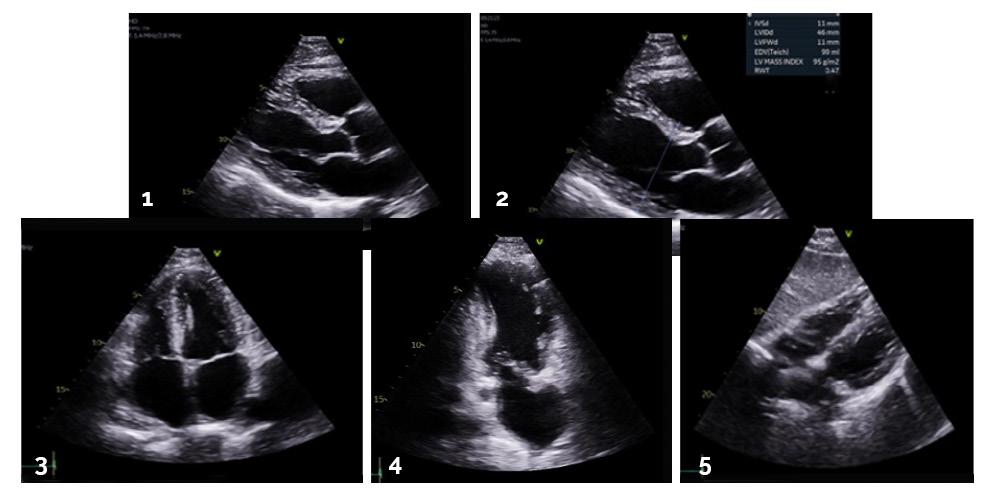

Pour établir un bon diagnostic en échographie cardiaque, nous devons constamment adapter notre perspective. Tout d’abord, l’information fournie par le médecin traitant, ainsi que les renseignements cliniques inscrits sur la requête (souvent à l’écriture illisible), nous permettent de cibler nos recherches et préparer notre examen. Ensuite, les questions du patient peuvent parfois nous diriger vers d’autres pistes pertinentes. La technique utilisée, quant à elle, est en fonction de l’état de santé du patient, mais aussi de la morphologie de son cœur, pouvant être complètement différente chez certains patients ayant une pathologie congénitale, par exemple.

L’ultrasonographie cardiaque est une modalité complexe de l’imagerie. Le cœur du patient est analysé sur tous les angles possibles. Conséquemment, le patient doit se tourner sous tous les côtés et adopter différentes positions. L’anatomie et la physiologie du cœur sont explorées sur tous les plans, afin que toute anomalie existante soit détectée. Nous espérons toujours trouver celle que d’autres technologues n’ont pas décelée, tout en gardant un visage impassible devant le patient. Pour ce dernier, une nouvelle perspective peut faire la différence entre la vie et la mort.

L’imagerie cardiaque est un défi pour plusieurs raisons. Une routine de base est établie pour ce type d’examen. Elle consiste en des vues parasternales, long et court axe, ainsi qu’en des vues apicales et souscostales (figure 1). L’anatomie et la fonction des valves et des ventricules sont étudiées. La fraction d’éjection, les gradients aortiques, mitraux, tricuspides et pulmonaires sont tous des aspects qui sont évalués et mesurés en cours d’examen. Les pathologies complexes observées seront imagées de façon encore plus détaillée dans le but de les définir davantage, souvent en utilisant des fonctions d’intelligence artificielle sur les appareils, par exemple, par imagerie du strain myocardique (figure 2).

L’anatomie et les pathologies cardiaques de chaque patient déterminent le nombre d’images que les technologues doivent produire. Ce nombre se situe très souvent entre 80 et 100. De plus, la santé générale du patient influe sur la durée de l’examen, variant en moyenne entre 45 et 60 minutes.

Un autre facteur important ayant une portée sur la qualité de l’examen ainsi que sa durée est l’impédance acoustique. Cette propriété se définit par le caractère

acoustique des tissus, dictant leur niveau de réflexion des ultrasons, et donc leur échogénicité. Celle-ci est variable d’un patient à l’autre et ne dépend ni de la volonté du patient ni de la capacité du technologue. Toutefois, certains aspects y sont directement liés, comme entre autres choses, l’épaisseur à traverser entre la sonde et les organes à observer. À titre d’exemple, plus la masse pondérale est élevée, plus la distance à traverser est grande et plus l’échogénicité est réduite.

Les patients n’ont pas tous la même échogénicité, et, par conséquent, la qualité des images produites n’est pas la même pour chacun. Par exemple, certains patients ont des valves sténosées qui seront remplacées par des valves mécaniques, tandis que d’autres patients ont des espaces intercostaux trop petits, ce qui provoque des cônes d’ombre.